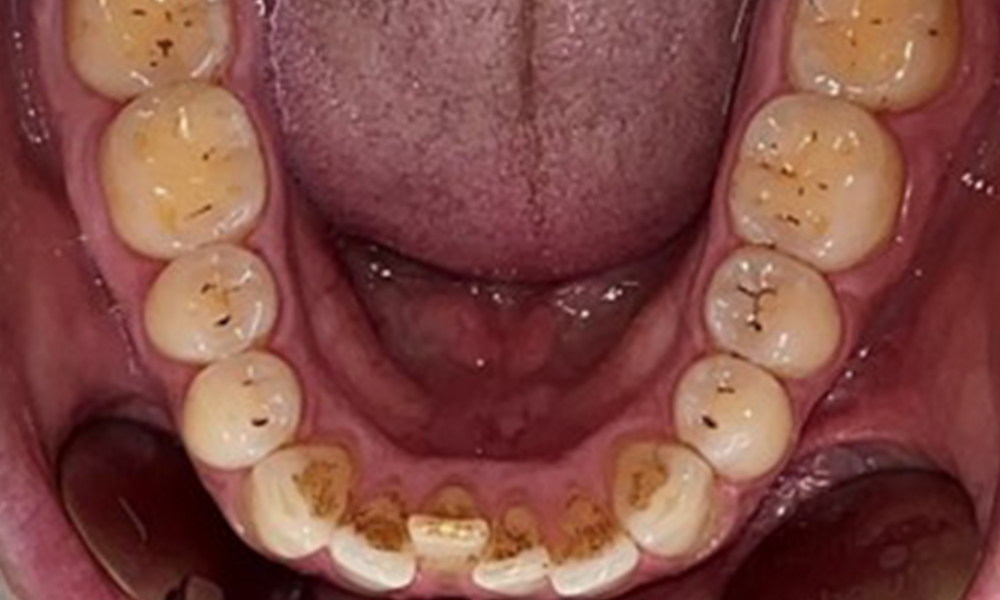

Observații la nivel dentar

Pacientul prezintă o dentiție completă, cu 28 de dinți. Se remarcă eroziuni și atriții. (Fig. 4, Fig. 5). Datorită bruxismului, timp de mulți ani, pacientul a purtat gutieră pe timp de noapte. Eroziunile sunt cauzate de consumul prelungit de băuturi izotonice. Nu au fost observate pierderi osoase de natură parodontală sau carii active.